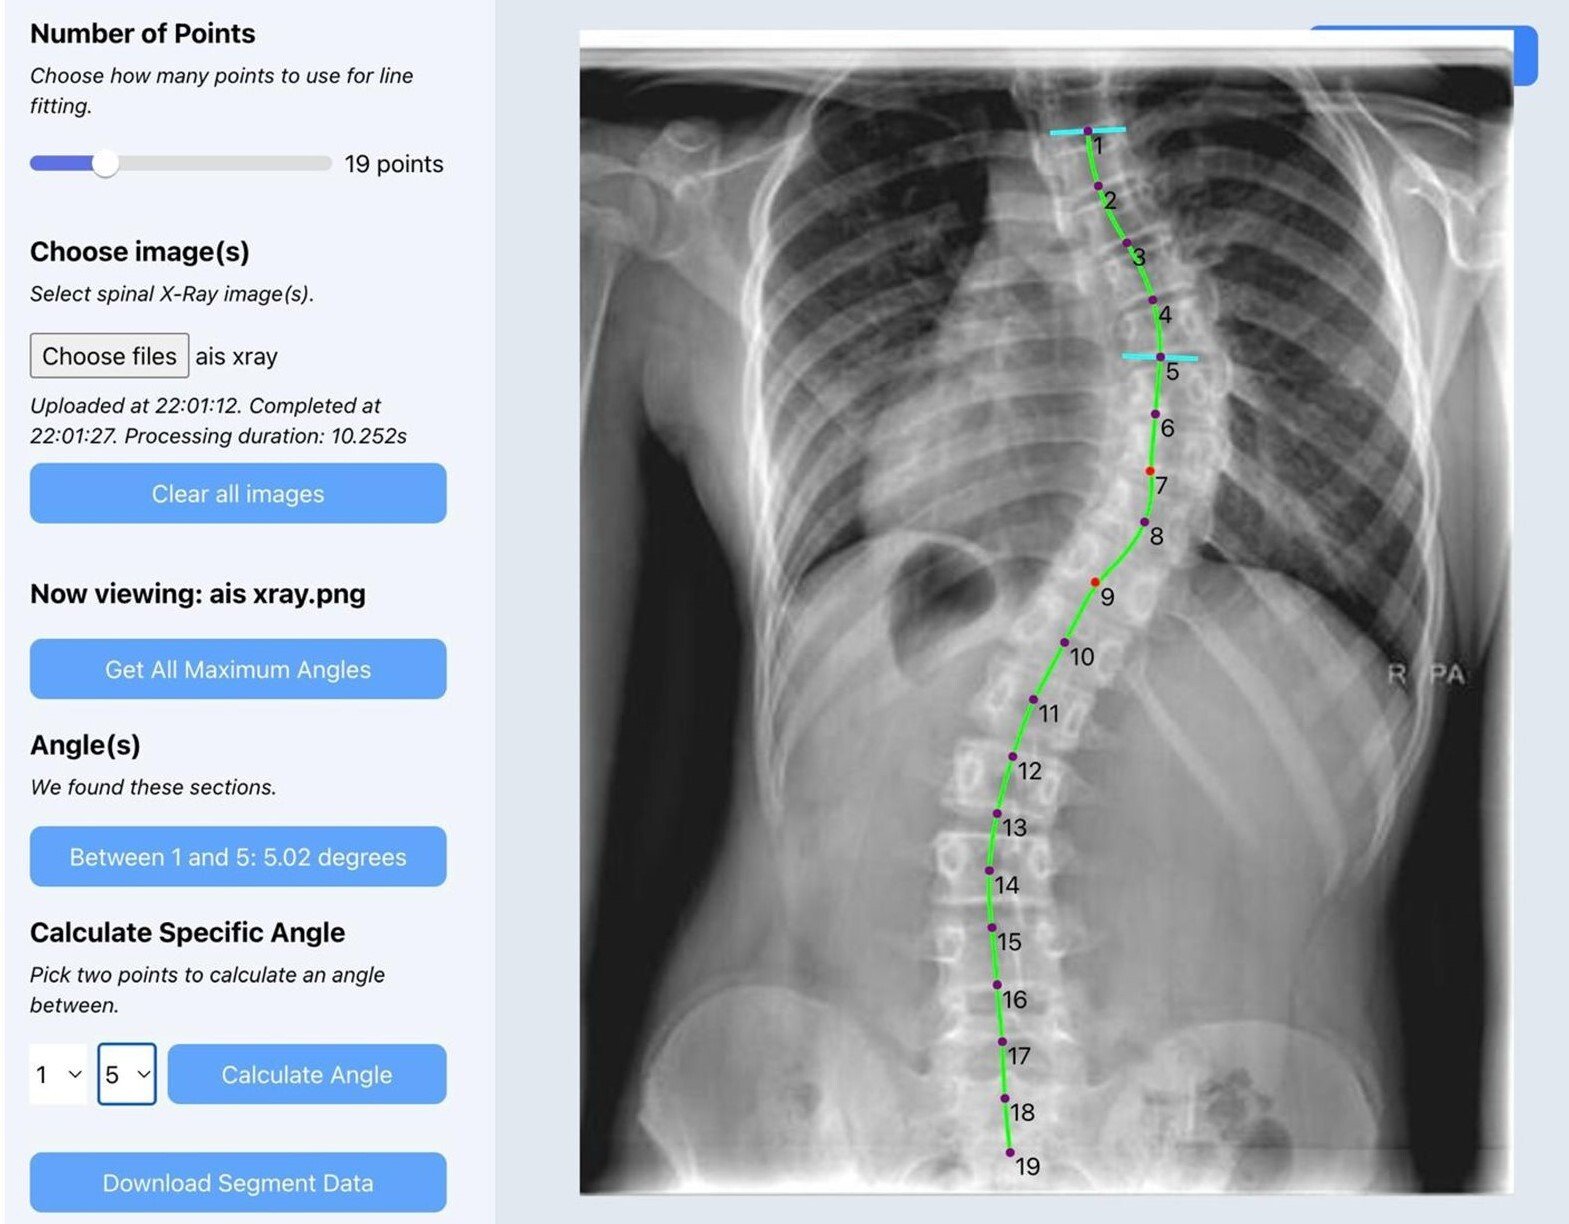

Automating Cobb Angle Measurement in Adolescent Idiopathic Scoliosis

This study demonstrates how computer vision can automatically measure Cobb angles from spinal radiographs, improving efficiency and consistency in scoliosis evaluation.